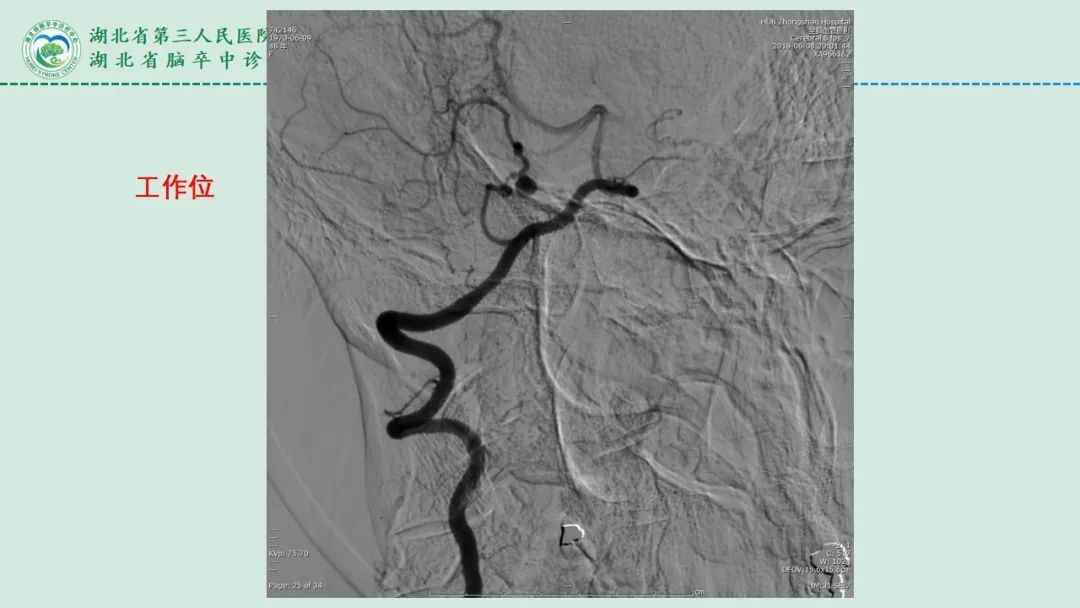

李俊教授团队:右侧PICA延髓扁桃体段多发动脉瘤

今日与大家分享的是《正海-妙术视界》第二百三十二期,由湖北省第三人民医院李俊教授团队带来的右侧PICA延髓扁桃体段多发动脉瘤,欢迎观看、分享。